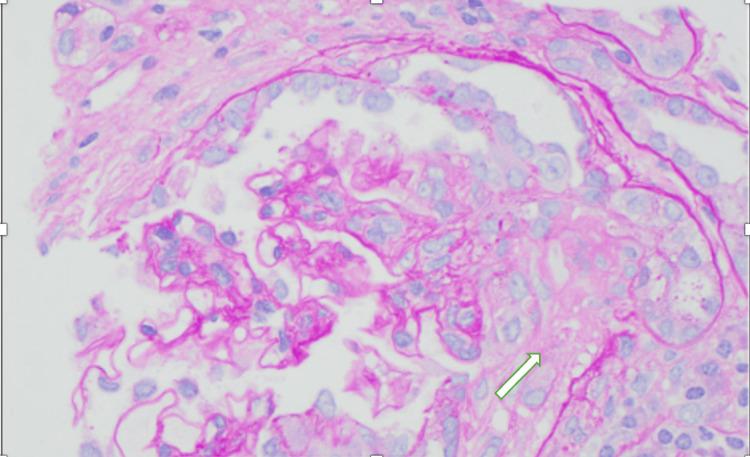

We present a rare case of hydralazine-induced antineutrophil cytoplasmic antibody (ANCA) vasculitis and lupus, characterized by the simultaneous and severe involvement of multiple organ systems. Following outpatient hydralazine dose escalation, a 77-year-old woman developed hypoxic respiratory failure secondary to diffuse alveolar hemorrhage, acute kidney injury with crescentic glomerulonephritis, and pancytopenia. Serologic testing revealed positive antinuclear antibody (ANA), dsDNA, anti-histone antibody, and P-ANCA, supporting the diagnosis of drug-induced autoimmune syndrome. This case highlights the risk for severe multi-organ dysfunction in drug-induced lupus and vasculitis, emphasizing the need for vigilance in recognizing such complications.

我们报告一例罕见的由肼屈嗪诱发的抗中性粒细胞胞浆抗体(ANCA)血管炎和狼疮病例,其特征为多个器官系统同时且严重受累。在门诊逐步增加肼屈嗪剂量后,一名77岁女性出现了因弥漫性肺泡出血继发的低氧性呼吸衰竭、伴有新月体性肾小球肾炎的急性肾损伤以及全血细胞减少。血清学检测显示抗核抗体(ANA)、双链DNA、抗组蛋白抗体和P-ANCA呈阳性,支持药物诱发的自身免疫综合征的诊断。该病例突出了药物诱发的狼疮和血管炎中严重多器官功能障碍的风险,强调了在识别此类并发症时保持警惕的必要性。